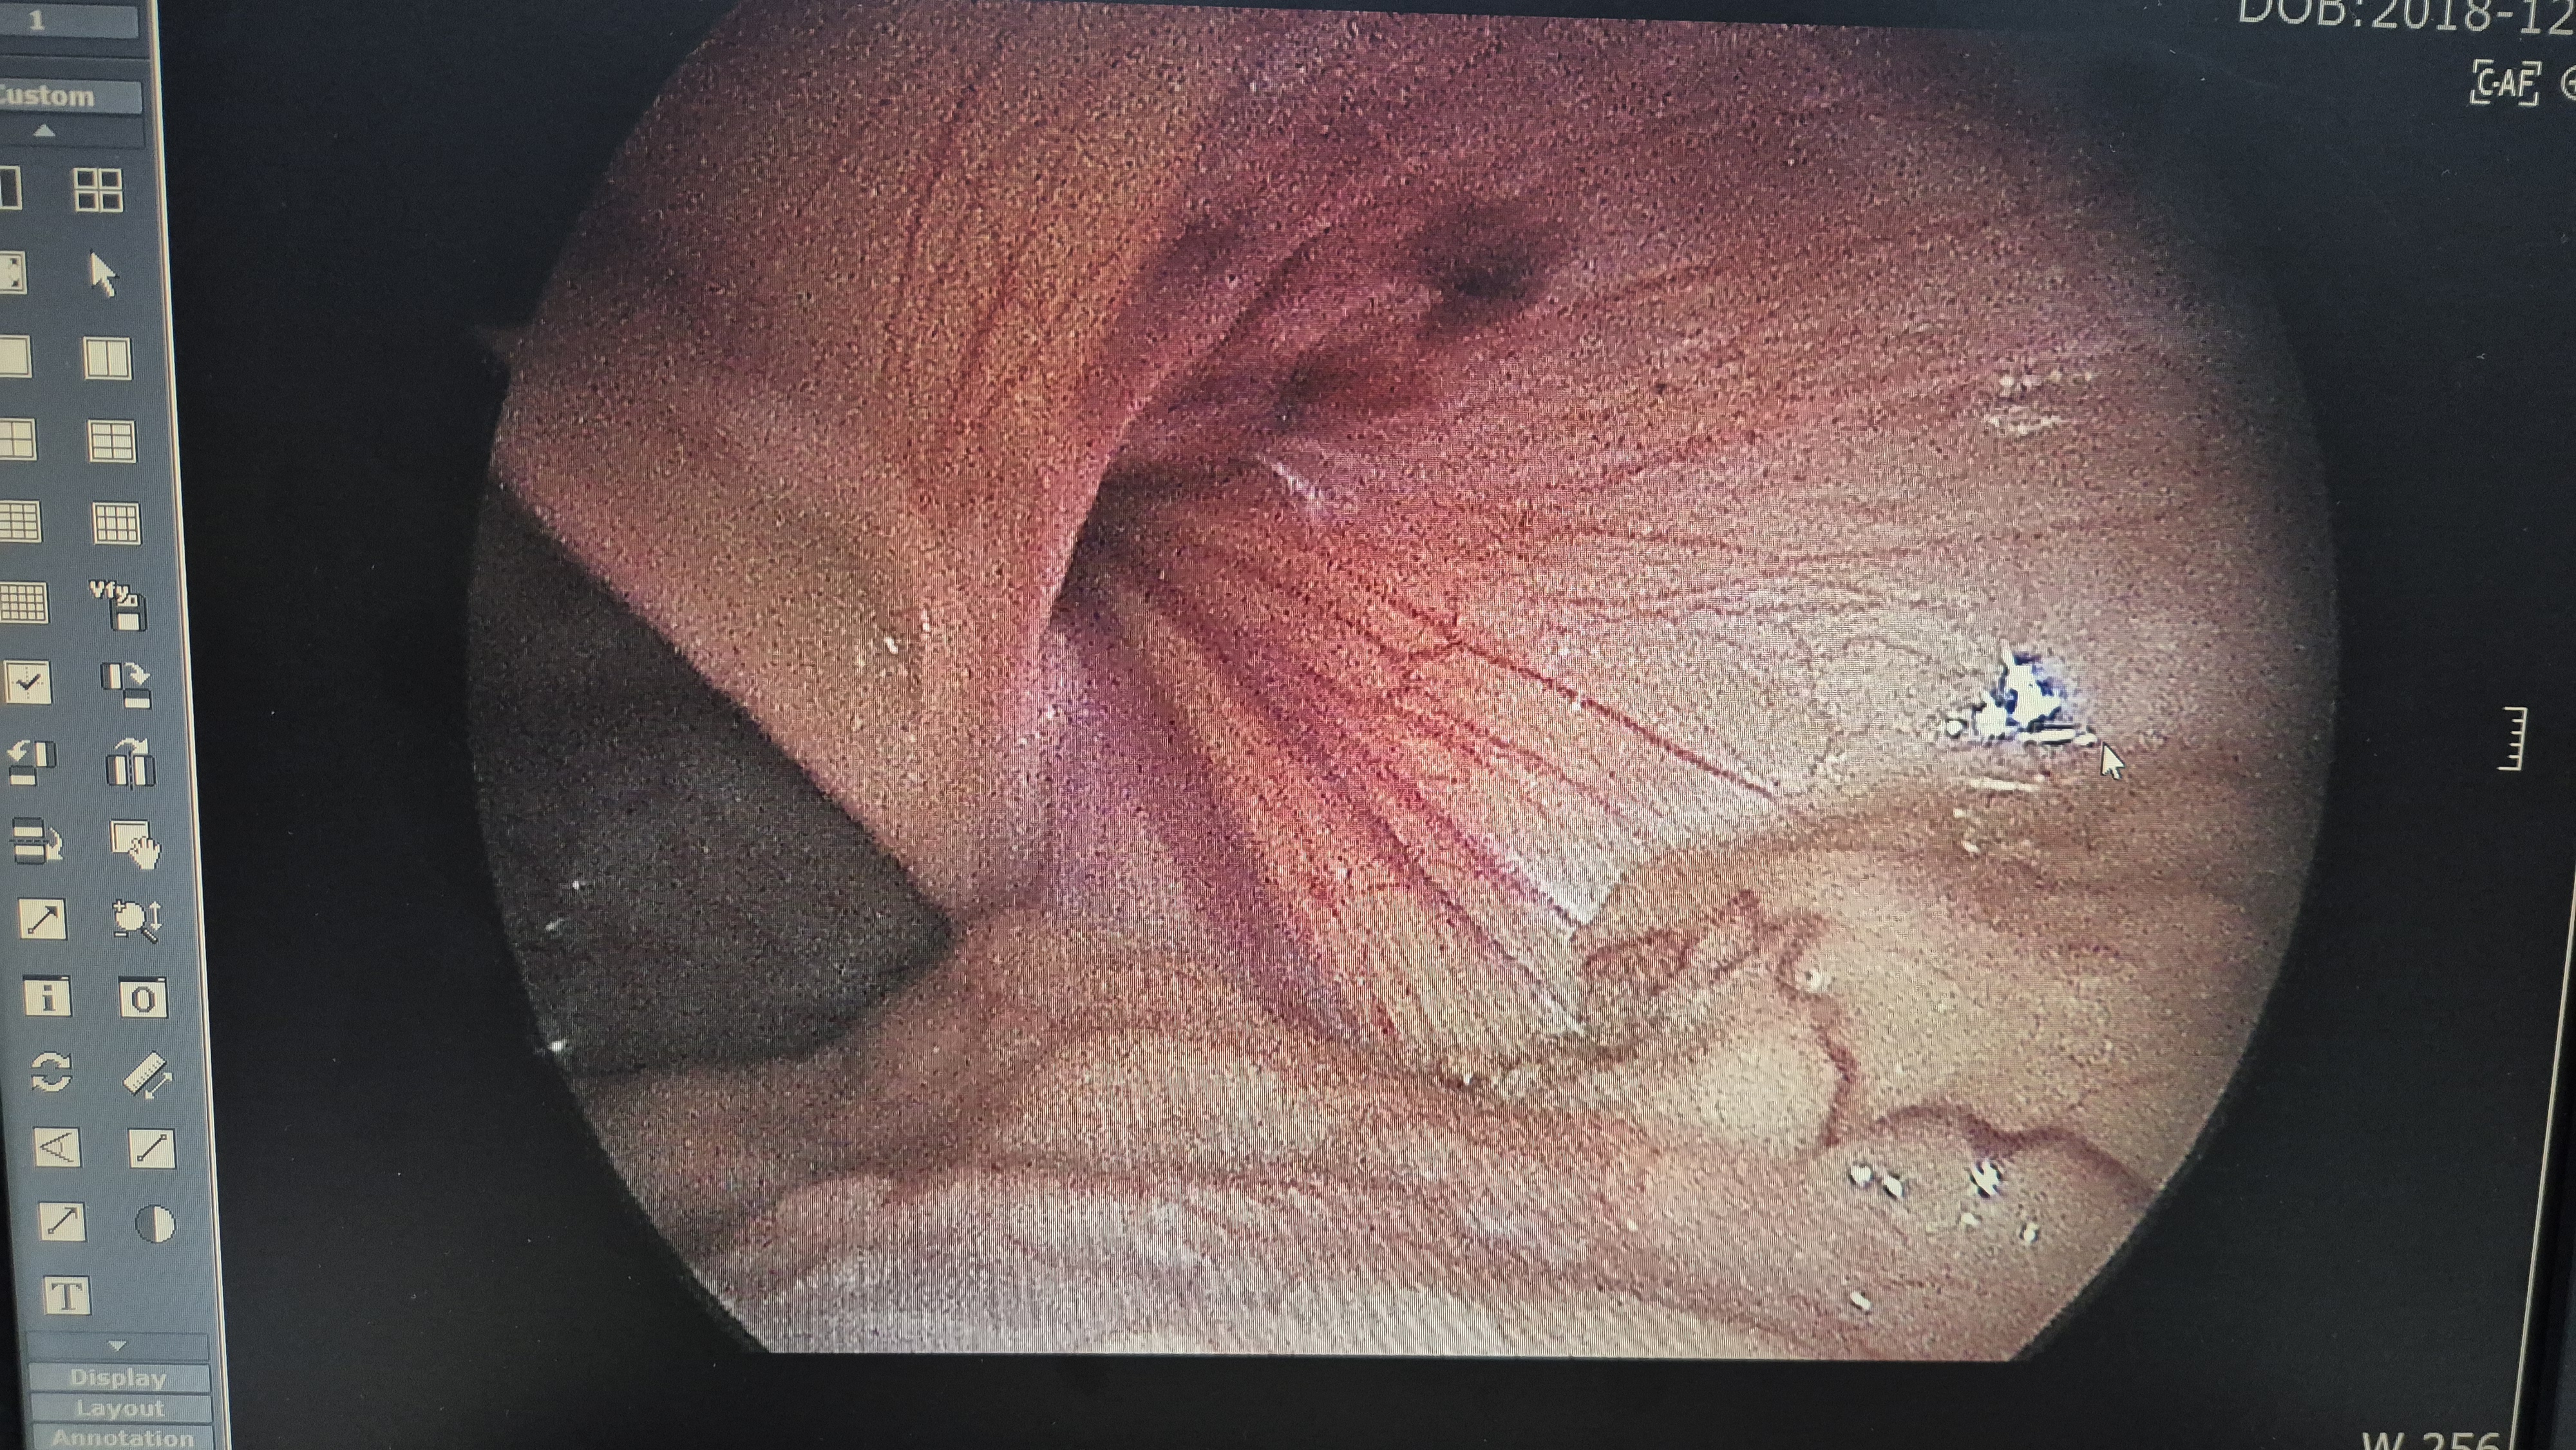

감돈 복원후.